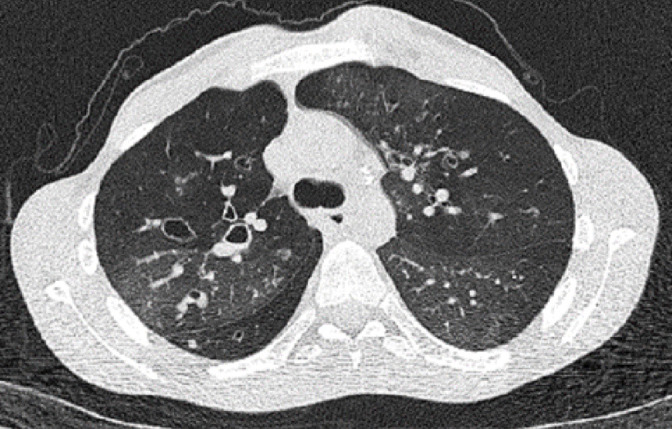

Results: Sixteen patients were enrolled. Median age at diagnosis was 27.5 months (range: 7-195 months). Wheezing was the most common presenting symptom. The most prevalent finding on thoracic CT was a mosaic pattern. In all but one, a wide range of variations genes related to both pulmonary structure and function were identified. The genes identified included those related to primary ciliary dyskinesia (DNAH genes), surfactant metabolism disorder (ABCA3, CSF2RB), pulmonary fibrosis (MUC5B, SFTP), and bronchiectasis (SCNN1B).